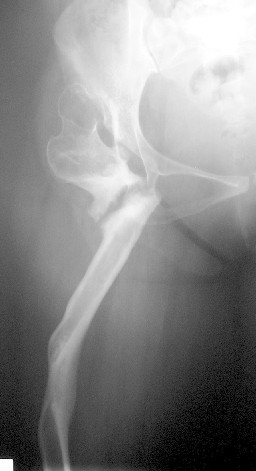

A 30-year-old female patient, presented with pain and limping post hip surgery and lengthening using Ilizarov technique 2 years duration.She said she had only limping preop. now she has painful limping and she can't walk without using walking aid.

Her X-ray --> non-union at the osteotomy site,pelvic tilt,bowing of the femur.clinically painful mobile pseudoarthrosis, LLD =4CM. Could those colleagues using such type of osteotomy Ilizarov method give us the clues how to treat such problems?Does this type of osteotomy still practiced by the group?Dr.Freih Odeh Abu Hassan,M.D(Orth.), F.R.C.S(Eng.), F.R.C.S.(Tr.&Orth.),Asst.Professor of Orthopedics Surgery,Jordan University - Amman.

Это вариант лечения по Илизарову при врожденном вывихе бедра у взрослых. Основан на методе Шанца (создание упора под впадину - вот как раз где не срослось), дополненный удлинением дистально с восстановлением механической оси бедра.

This operation - the Ilizarov Hip Reconstruction consists of an extreme valgus osteotomy in the proximal femur, to stabilise the unstable hip, a lengthening distally to equalise the limb lengths, and a varusization thru that lengthening zone to bring back the distal limb parallel to the other limb, and normalise the "mechanical axis".

Treatment now would need to be by the use of an ilizarov fixator and bone grafting on the concave portion of the proximal femur rather than between the bone ends actually.